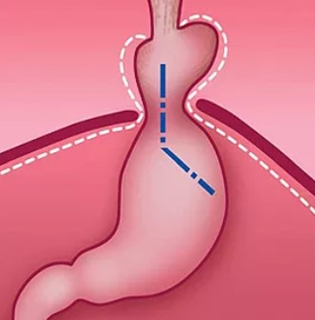

Перемещение части желудка в грудную полость и изменение угла Гиса при грыже пищеводного отверстия диафрагмы (схема).

Под действием различных факторов связки, фиксирующие желудок и пищевод, растягиваются, соотношение между пищеводом и желудком изменяется. В результате часть желудка и пищевода, чаще при изменении положения тела, свободно перемещаются через расширенное отверстие диафрагмы в полость грудной клетки и возвращаются обратно.

При этом полностью сглаживается угол Гиса — в норме это острый угол, образованный при впадении пищевода в желудок. Это анатомическое образование препятствует обратному забросу пищи из желудка в пищевод. В результате изменения угла Гиса и нарушения функции нижнего сфинктера пищевода содержимое желудка или желчь свободно попадают в пищевод. Обладая агрессивными свойствами, содержимое действует на слизистую оболочку, в результате чего развивается воспалительный процесс в пищеводе — рефлюкс-эзофагит.